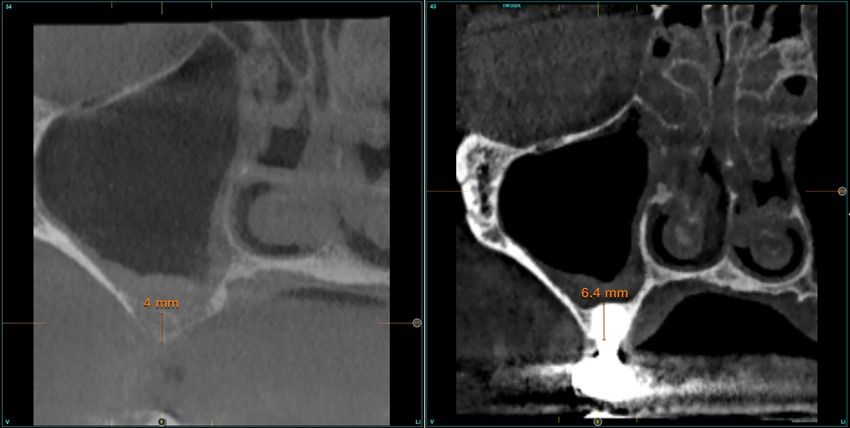

Resultados. Fueron reclutados 13 pacientes en los que se insertaron 30 implantes. Una vez insertados y cargados los implantes, la altura media final fue de 9,68 mm (+/- 2,66), lo que supone una ganancia promedio de 5 mm. A los 10 años, se observó una disminución media de la altura ósea ganada en los implantes en conjunto de 0, 29 mm (+/- 0,77). La media de la pérdida ósea mesial fue de 0,73 mm (+/- 0,75 mm) y la media de la pérdida ósea distal fue de 0,98 mm (+/- 1,2 mm). La supervivencia fue del 100%.

Results.Thirteen patients were recruited and 30 implants were inserted. Once the implants were inserted and loaded, the mean final height was 9.68 mm (+/- 2.66), which represents an average gain of 5 mm. At 10 years, there was a mean decrease in the overall bone height gain of the implants of 0.29 mm (+/- 0.77). The mean mesial bone loss was 0.73 mm (+/- 0.75 mm) and the mean distal bone loss was 0.98 mm (+/- 1.2 mm). Survival was 100%.

Nuestro grupo de estudio modifica esta técnica de elevación transcrestal utilizando para el acceso unas fresas de corte frontal que permiten eliminar la cortical inferior del seno con lentitud sin dañar la membrana de Schneider, eliminándose los osteotomos y el malestar que genera su accionamiento mediante el martillo6-7. Inicialmente el procedimiento fue concebido para ser empleado con material de injerto al igual que el abordaje convencional, pero posteriormente se presentaron variaciones del procedimiento donde se insertaban los implantes sin injerto, utilizándose el propio implante como mantenedor de espacio entre la membrana de Schneider y la cavidad creada entre la membrana y la cresta, permitiendo que esta cavidad no se colapsase y posteriormente fuera colonizada por nuevo hueso7-11.

Los senos tratados con la técnica de elevación transcrestal sin material de relleno muestran un incremento de entre 2,5 mm12,13 hasta 4.4 mm14,15 en la altura ósea lograda sobre el ápice y una supervivencia de los implantes que se sitúa entre un 94 y un 100%16-17. En este trabajo se presenta un estudio retrospectivo donde se ha evaluado la inserción de implantes extracortos (5,5 y 6,5 mm) en zonas posteriores maxilares mediante la técnica de elevación de seno transcrestal con la fresa de ataque frontal sin la utilización de material de injerto, con un tiempo de seguimiento de 10 años para poder objetivar el comportamiento de los implantes a largo plazo y de la técnica empleada.